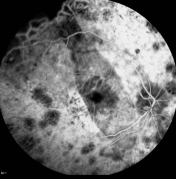

The Eye Institute of The University of Hong Kong (HKU) Li Ka Shing Faulty of Medicine performed the first implantation of subretinal microchip in Asia to a Chinese patient who was visually impaired due to degenerative condition retinitis pigmentosa (RP). The early result of the surgery is highly satisfactory and the patient has gained sight, including seeing light and dark and being able to read letters projected on a screen. The microchip was developed by Retina Implant AG ("Retina Implant"), a leading developer of subretinal implants for the visually impaired. Subsequent to the first and second phases of clinical trials conducted in Germany, the operation performed by HKU team is the first successful case outside Germany to apply the new technology on a patient, kicking off the phase 3 international trial of this subretinal implants.

The patient, Mrs TSANG WU Suet-yun, has been legally blind for 15 years. She experienced a sharp visional deterioration a few years before losing her eyesight. Prior to the surgery, she was able to see almost no light at all. Despite this, she had adapted to her condition and continued to live a very productive and capable life. She works as a masseuse and at home, prepares dinner for the family every day - in almost total darkness. Following the procedure in which she received Retina Implant's microchip, she can see light and dark. In the laboratory, she was even able to read letters projected on a screen.

The subretinal microchip implantation involves placing a 1500-electrode microchip just below the retina, specifically in the macular region. Results of Retina Implant's first human clinical trial were published in the prestigious peer-reviewed journal Proceedings of the Royal Society B and showed placement of the implant below the retina, in the macular region, provided optimum visual results allowing patients to recognize foreign objects and to read letters to form words.